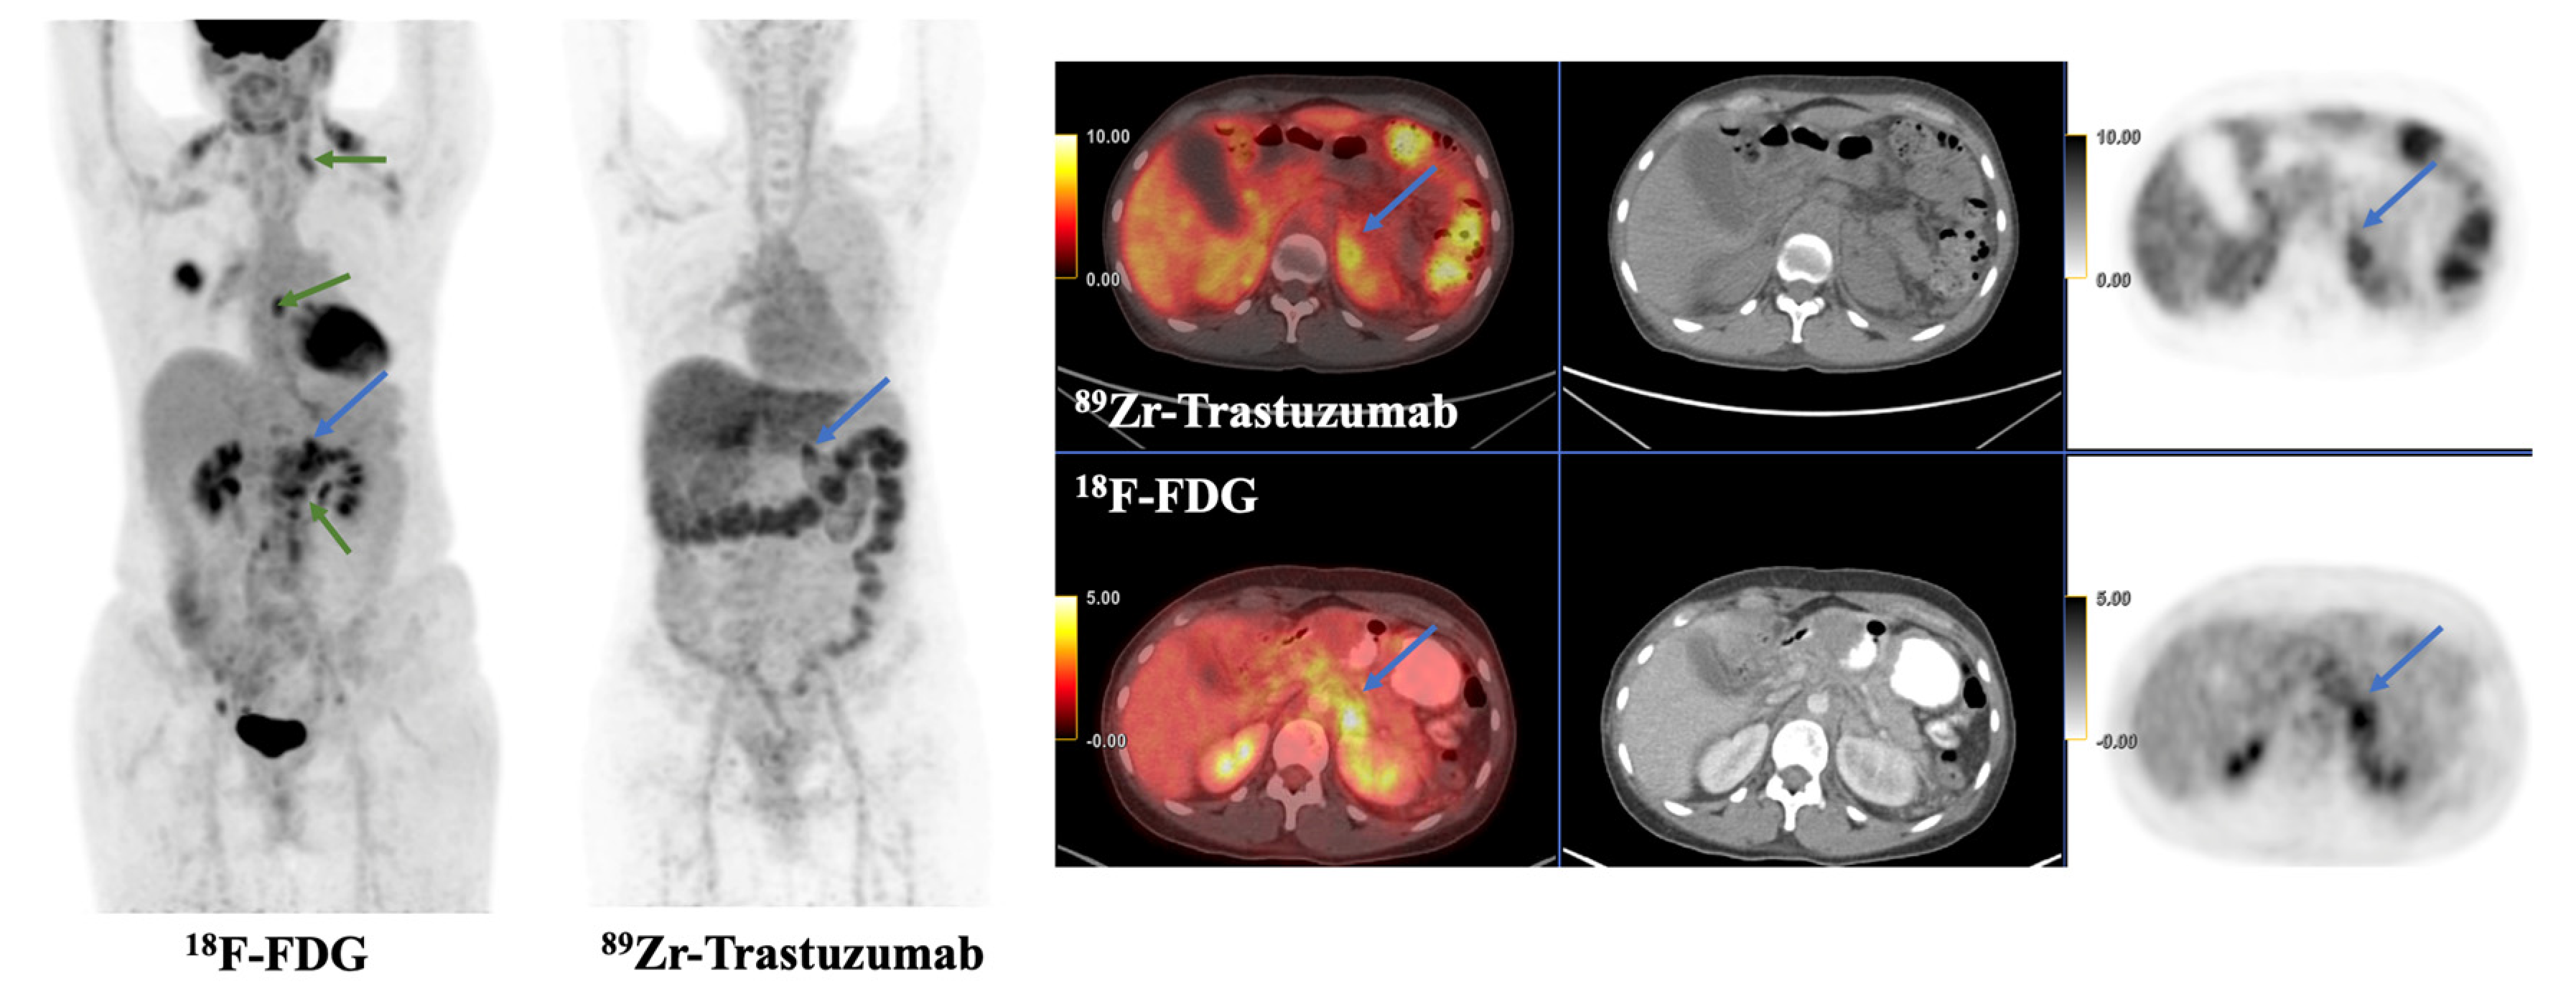

Diagnostic Imaging: Breast: 9780323548120: Medicine & Health。40134_2025_433_Fig4_HTML.png。40134_2025_433_Fig1_HTML.png。マンモグラフィーや超音波などの診断技術を網羅した、拡大改訂版の医学書。PET/CT and SPECT/CT Imaging of HER2-Positive Breast Cancer。- 書籍名: Diagnostic Breast Imaging- 著者: Sylvia H. Hewayng-Köbrunner, D. David Dershaw, Ingrid Scherer- 版: 第2版, 拡大改訂版- 出版社: Thieme- 内容: マンモグラフィー、超音波、磁気共鳴画像、介入手技に関する情報ご覧いただきありがとうございます。有限要素法。

• 40134_2025_433_Fig4_HTML.png

• 40134_2025_433_Fig1_HTML.png

• PET/CT and SPECT/CT Imaging of HER2-Positive Breast Cancer